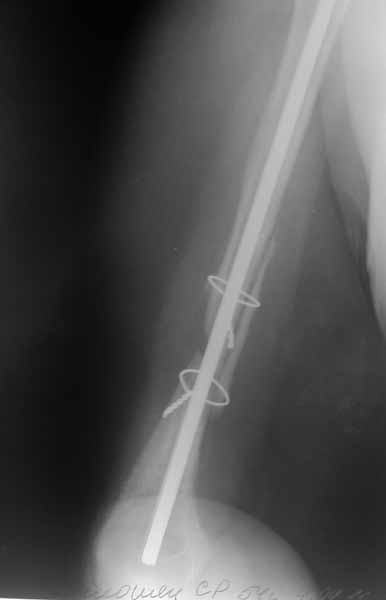

Re: Застарелый вывих головки плечевой кости

Прошу прощения за отсутствие всех рентгенограмм.

Выбрасываю. По поводу гипсовой повязки: пациентка находилась в повязки типа Дезо. Плечо в приведении.